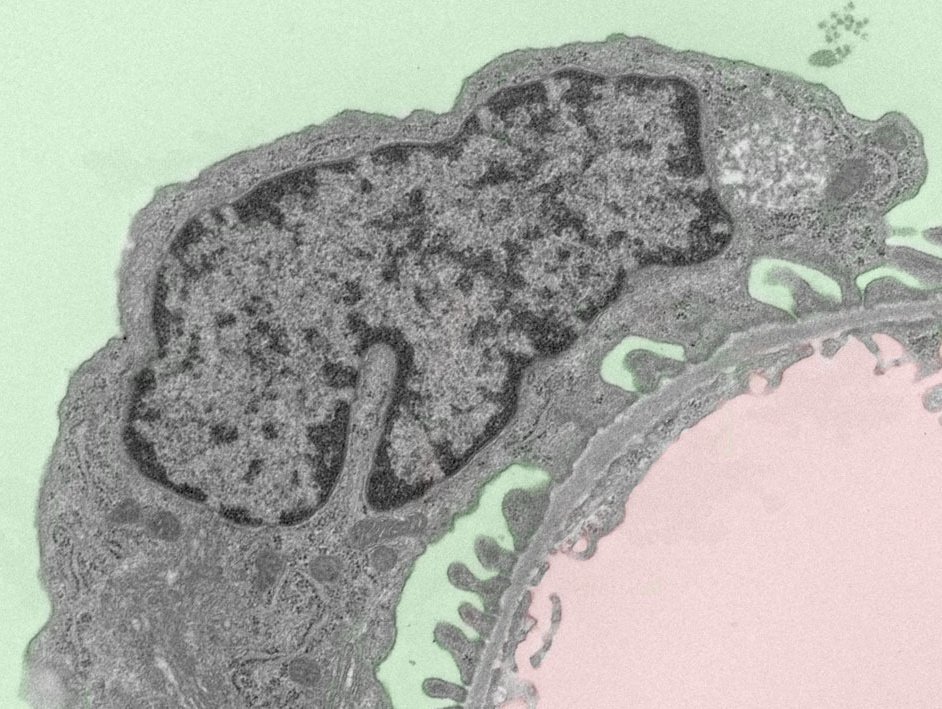

透射电子显微镜

TEM:Transmission Electron Microscopy

以最高水平的空间分辨率实现细胞内部的微观结构解析

Analysis of the fine structure of cells with high resolution